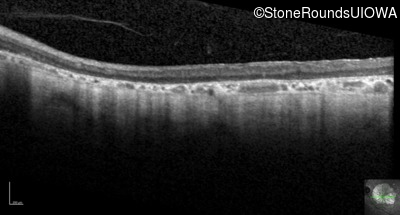

Optical Coherence Tomography - Right - 20/160 +2 sc

Exemplar / OCT Stack

Optical Coherence Tomography - Left - 20/160 sc